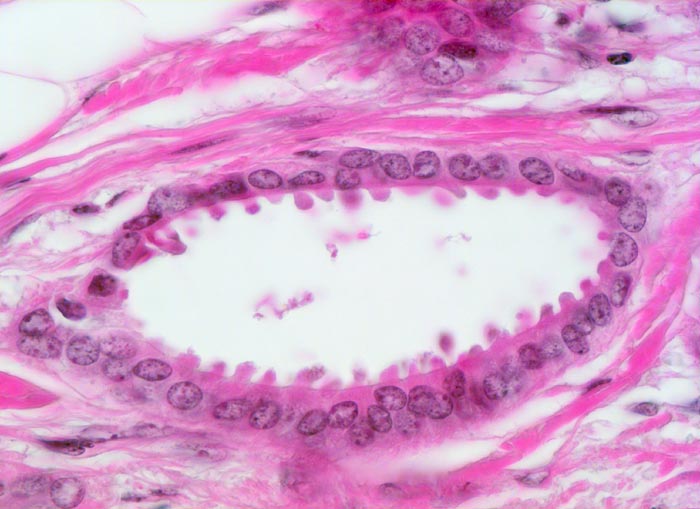

tubuläres Karzinom

maligner Tumor

Mamma

Tubuläre einreihige Karzinomdrüse ohne Basalmembran. Die Tumorzellen zeigen auffallende apikale Ausziehungen des Zytoplasmas (Snouts). Die Tumorzellkerne sind auffallend bland. Eine Myoepithelschicht fehlt.

Positive Familienanamnese für Mammakarzinom. Tumorverdächtiger Herd in der rechten Mamma.

Histologie

400